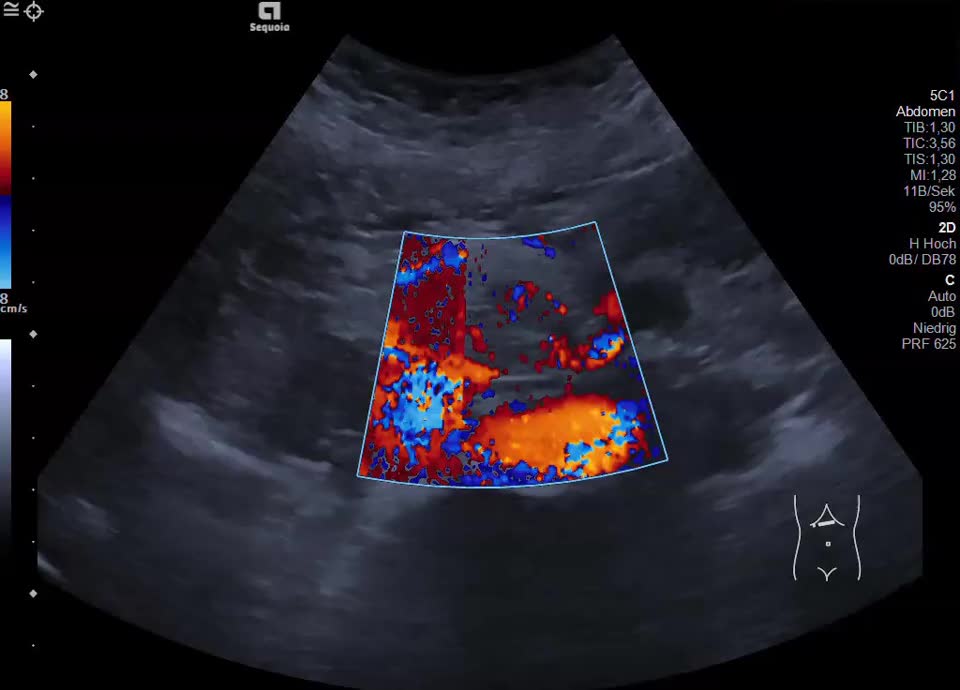

Case

60-year-old female patient with incidental finding of serous cystadenoma one year ago. Current follow-up examination reveals small cystic mass (honeycomb pattern visible on EUS) of constant size in the head of the pancreas/uncinate process. In the transcutaneous B-scan, central echogenic portion (central scar), hypervascularized on color Doppler sonography.